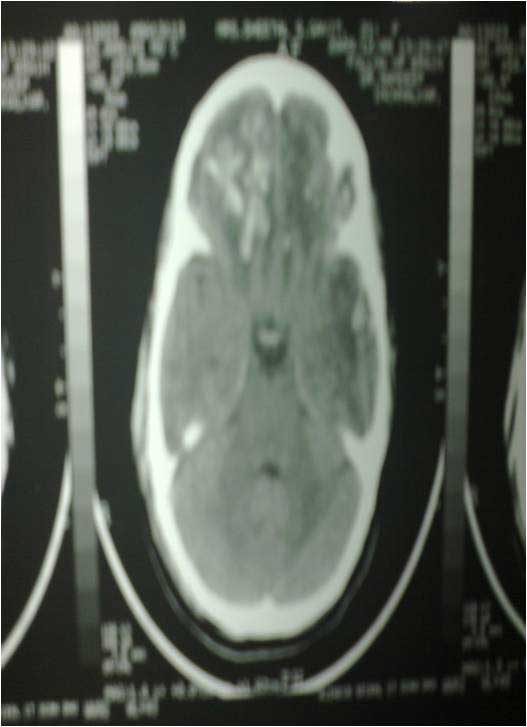

Brain Contusion Post OP CT of Bifrontal Contusion Brain X-Ray Bifrontal Contusion Pre OP intra op photo of contusion Brain Abscess Post OP 2 Clinical Brain Abscess Post OP 2 Clinical Brain Abscess Post OP 2 Clinical Brain Abscess Post OP 2 Clinical Brain Abscess Post OP 2 Clinical Brain Abscess Post OP 2 Clinical